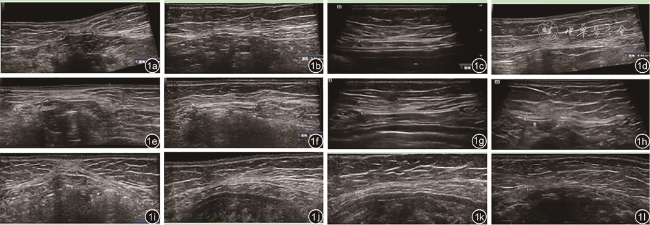

二、仪器与方法